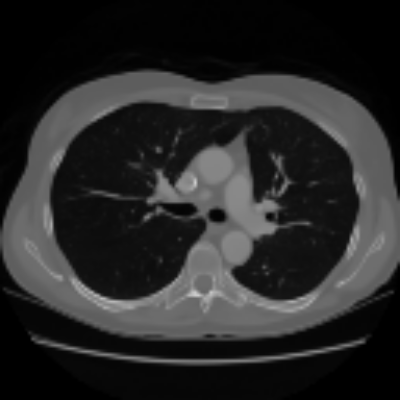

| Axial | Coronal | Sagittal | |

| X2CTGAN | ![]() |

![]() |

|

| DX2CT | ![]() |

| Ground-truth | ![]() |

Figure 3 and Table I(a) using biplanar X-rays show that proposed DX2CT can outperform three existing SOTA methods. Figure 3 shows that DX2CT can provide more accurate overall shapes and details compared to the existing methods. The quality of reconstructed CT slices in the axial plane is less satisfactory than those in the other planes. The reason is that the axial plane is perpendicular to the planes of biplanar X-rays so there exists less spatial (i.e., depth) information in the axial plane. Without using the perceptual loss [33], proposed DX2CT gave comparable LPIPS results with PerX2CTs using [33] in training. Compare their LPIPS results in Table I(a).